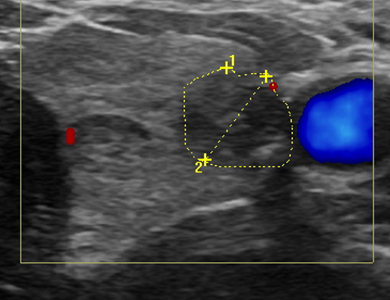

°©»ó¼±/µÎ°æºÎ(¸ñ) ÃÊÀ½ÆÄ

°©»ó¼±, ¸²ÇÁÀý, ħ»ù µî Ȥ(Á¾¾ç)ÀÌ ÀÖÀ» ¶§ ȤÀÇ Á¾·ù¸¦ ÆÄ¾ÇÇϰí,

¾ÏÀÇ ¿©ºÎ¸¦ ¹àÈ÷±â À§ÇÑ °Ë»çÀÔ´Ï´Ù.

Á¶Á÷ äÃë

¾ÈÁ¤ ÈÄ ±Í°¡

ÁÖ»ç±â ¶Ç´Â Á¶Á÷»ý°Ë¿ë ÃÑÀ» ÀÌ¿ëÇÏ¿© °Ë»ç½Ã ÃÊÀ½ÆÄ ¿µ»óÀ» º¸¸é¼­ Àǻ簡 ½Ã¼ú¹Ù´ÃÀ» Ȥ¿¡ ³Ö°í ¼¼Æ÷ ¶Ç´Â Á¶Á÷À» äÃëÇÕ´Ï´Ù.

Çʿ信 µû¶ó ±¹¼Ò¸¶Ã븦 ½ÃÇàÇÒ ¼ö ÀÖÀ¸¸ç, ȤÀÇ °³¼ö¿Í Á¾·ù¿¡ µû¶ó ¸îÂ÷·Ê ´õ °Ë»çÇÒ ¼ö ÀÖ½À´Ï´Ù.

°Ë»ç°¡ ³¡³­ ÈÄ ¾óÀ½ÁÖ¸Ó´Ï ¹× ±¹¼Ò¾Ð¹Ú°ú °°ÀÌ ¾ÈÁ¤À» ÃëÇϽŠµÚ ±Í°¡ÇÕ´Ï´Ù.

°æ¿ì¿¡ µû¶ó 15~30ºÐ °¡·®ÀÇ ¾ÈÁ¤ÀÌ ÇÊ¿äÇÒ ¼ö ÀÖ½À´Ï´Ù.